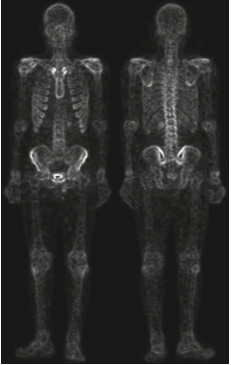

실제로 일반적인 샤프닝 영상에 비해서 훨씬 깔끔한 영상을 얻은 것을 볼 수 있습니다. 하지만 여전히 밝기값이 낮기 때문에 마지막으로 거듭제곱-법칙 변환을 적용해여 아래의 최종 영상을 얻을 수 있습니다.

위의 과정이 의미하는 바는 단일 기법으로는 가능하지 않은 결과를 얻기 위해서 결합될 수 있는 프로세스들이 있음을 의미합니다. 이때 어떤 프로세스들을 결합할 지는 어떤 문제를 해결하느냐에 달라지게 됩니다.